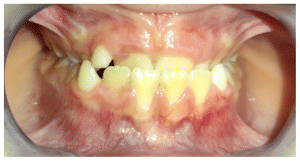

The patient was a young female presenting with a Class III dento-skeletal malocclusion, which was treated using the AMCOP® TC appliance. A comprehensive diagnostic protocol was carried out both before and after treatment, including orthopantomography (Figure 2–3), postero-anterior teleradiography (Figures 4, 5), latero-lateral cephalometric radiography (Figures 6, 7), cephalometric analysis (Tables 1, 2), as well as extraoral (Figures 8, 9) and intraoral photographs (Figures 10, 11). The extraoral examination revealed an edge-to-edge incisal relationship and the presence of a midline diastema. Pre-treatment cephalometric analysis (Deltadent® Lana, Bolzano, Italy) confirmed the diagnosis of a skeletal Class III malocclusion. The treatment plan involved the use of the AMCOP® TC appliance. The patient was instructed to wear the device for two hours in the afternoon and throughout the night for the first six months, followed by nighttime use only for an additional six months. Upon completion of the treatment, the patient achieved a Class I occlusion, with correction of both overjet and overbite. Additionally, the device facilitated tongue re-education and contributed to the postural realignment of the first cervical vertebra.